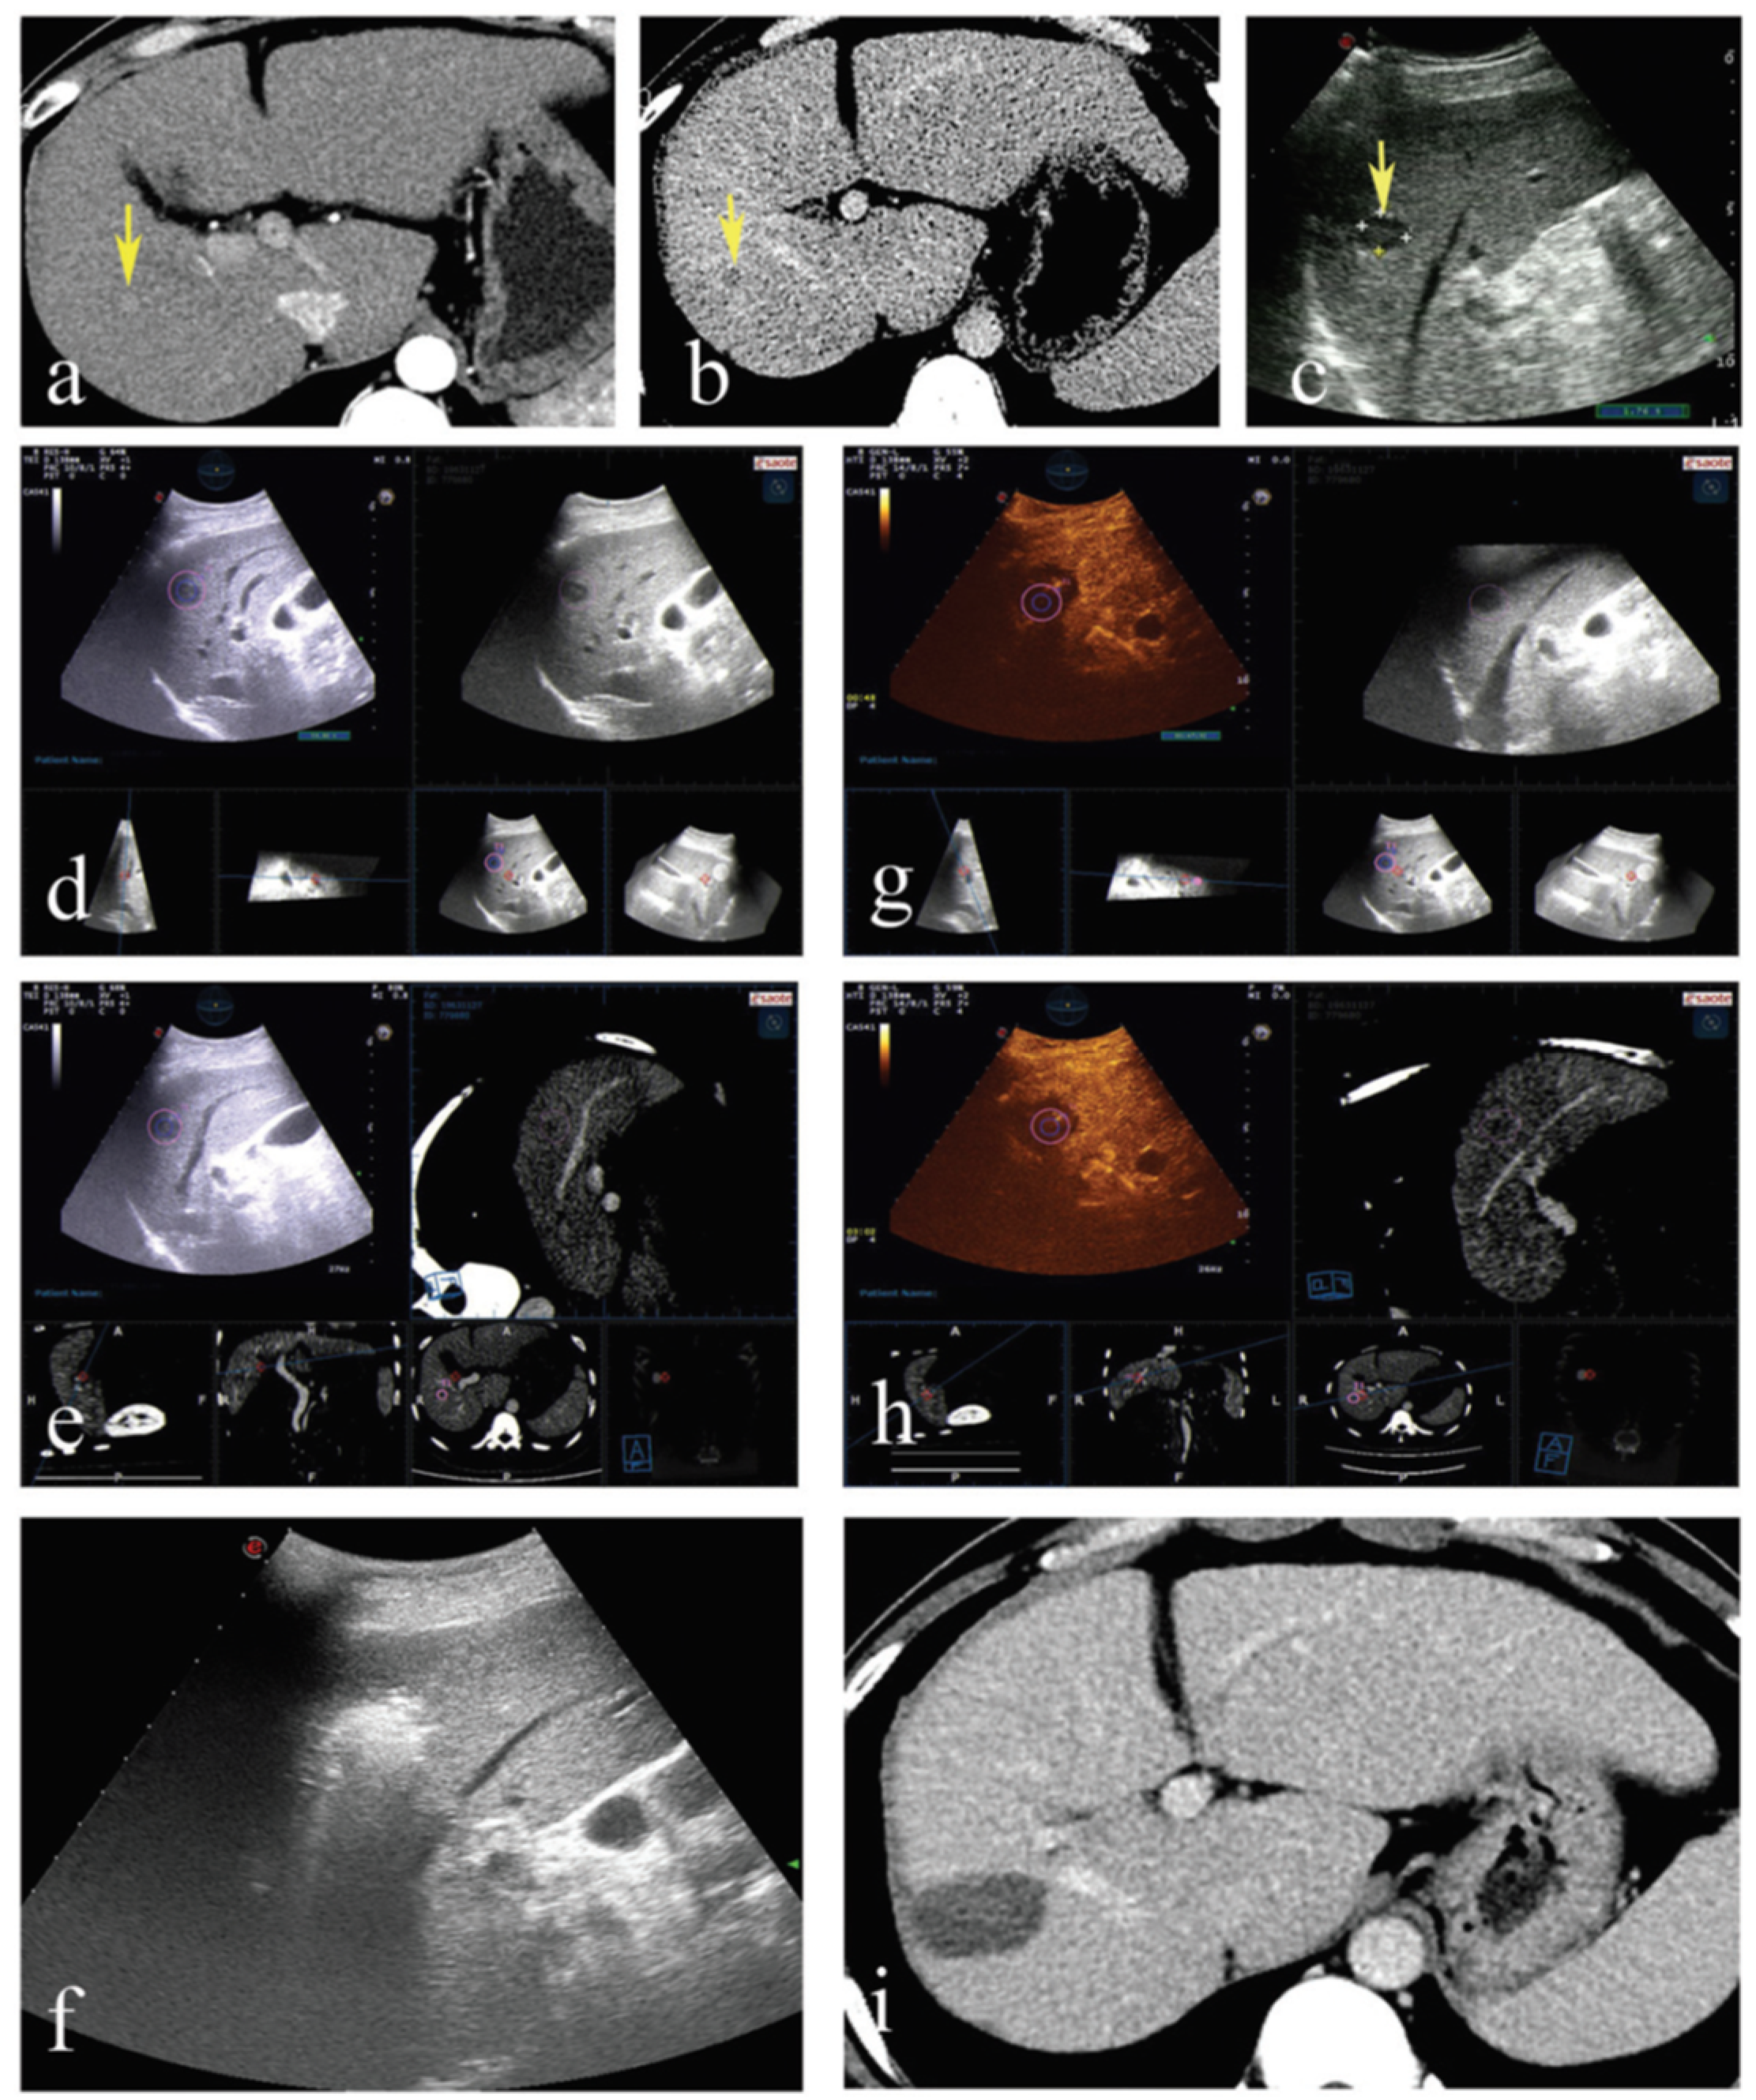

- Xu, E.; Long, Y.; Li, K.; Zeng, Q.; Tan, L.; Luo, L.; Huang, Q.; Zheng, R. Comparison of CT/MRI-CEUS and US-CEUS fusion imaging techniques in the assessment of the thermal ablation of liver tumors. Int. J. Hyperth. 2018, 35, 159–167. [Google Scholar] [CrossRef]

- Jung, E.; Schreyer, A.; Schacherer, D.; Menzel, C.; Farkas, S.; Loss, M.; Feuerbach, S.; Zorger, N.; Fellner, C. New real-time image fusion technique for characterization of tumor vascularisation and tumor perfusion of liver tumors with contrast-enhanced ultrasound, spiral CT or MRI: First results. Clin. Hemorheol. Microcirc. 2009, 43, 57–69. [Google Scholar] [CrossRef]